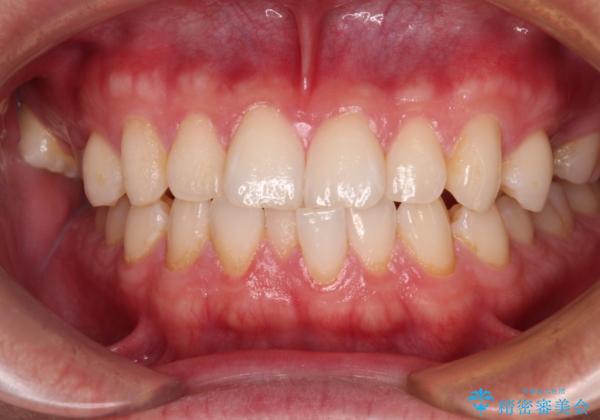

今回ご紹介するのは、「前歯のガタガタ(叢生)」と「奥歯のかみ合わせ(シザーズバイト)」にお悩みでご来院された患者様の症例です。

**前歯のデコボコ(叢生)**が整い、歯列全体が美しく改善

シザーズバイトの奥歯も正常なかみ合わせに改善

捻転歯も回転が修正され、全体的に清掃性・咀嚼効率が向上